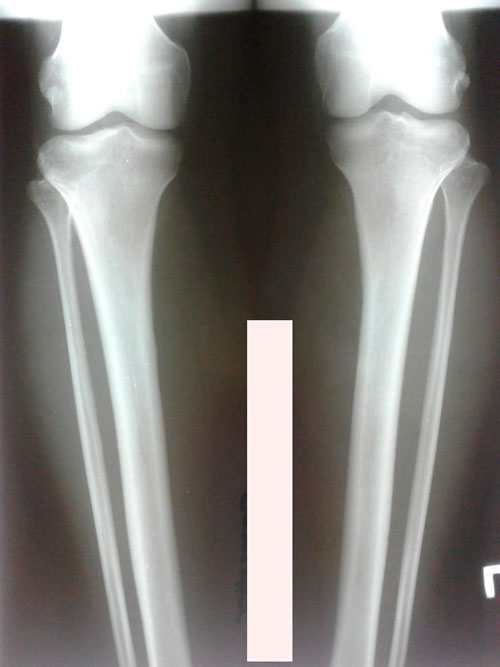

Исходник - 43 года.Астана.

Дата операции -21.11.2018г.

Вложения

IMG-20181119-WA0023.jpg

IMG-20181119-WA0025.jpg